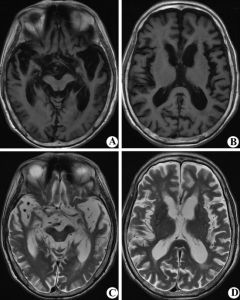

CT及MR(磁共振)等神經影像學檢查可發現腦組織體積減少、腦室擴大。如果大腦萎縮可見腦皮質與顱骨板間隙增大,大腦溝增寬增深、腦回變平縮小,側腦室及第三腦室擴大,側腦室前后角周圍密度減低。小腦萎縮時可顯示小腦腦溝增寬增深,體積縮小,影像呈現分枝樹葉狀,小腦周圍腔隙增大,第四腦室擴大。如果有橋腦橄欖體萎縮,在神經影像上可見腦幹變細狹窄,周圍腔隙增大、橄欖體變扁平或縮小。

科學研究表明,大腦最外層是呈灰色的大腦皮層,由140億個神經細胞體組成,厚3.5mm,大腦皮層表面曲折不平,有凹陷的腦溝和凸起的腦回,大腦皮層下面為白色的髓質。在腦的中部還有數個呈空隙的腦室。腦神經老化死亡後,腦的重量變輕,體積變小,CT檢查呈現腦體積縮小,腦溝變寬,腦回變細,腦室擴大,這就是腦萎縮。